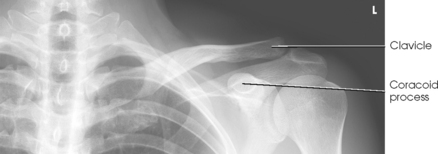

Structures shown: The image shows the bony and soft structures of the shoulder and proximal humerus in the anatomic position (Figs. 5-14 to 5-16). The scapulohumeral joint relationship is seen.

Fig. 5-14 A, AP shoulder, external rotation humerus: greater tubercle in profile (arrow). B, AP shoulder, neutral rotation humerus: greater tubercle (arrow).

External rotation: The greater tubercle of the humerus and the site of insertion of the supraspinatus tendon are visualized (see Fig. 5-14, A).

Neutral rotation: The posterior part of the supraspinatus insertion, which sometimes profiles small calcific deposits not otherwise visualized (see Fig. 5-14, B), is seen.

Internal rotation: The proximal humerus is seen in a true lateral position. When the arm can be abducted enough to clear the lesser tubercle of the head of the scapula, a profile image of the site of the insertion of the subscapular tendon is seen (see Fig. 5-15).